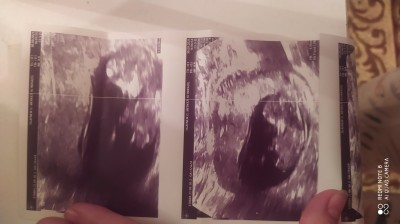

Bayanlar  bebeğimin cinsiyetini merak ediyorum doktor söylemedi 12+3 dedi programda 11+2 diyor şaşırdım

Gebelik haftası 12

Kapatılma nedeni: Cinsiyet tahminlerini sol üst köşeden konu dışı sohbetten sorabilirsiniz